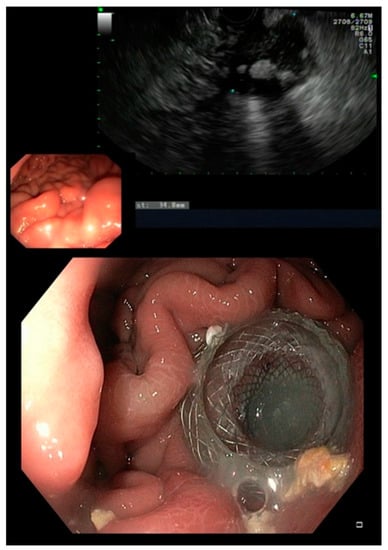

In our cohort, an endoscopic transmural approach was chosen in 25 patients (41.7% of all documented fistulas) of whom one patient also received a somatostatin analogue postoperatively. EUS-guided drainage using LAMS was the treatment of choice, whereas two patients received transmural drainage using only double-pigtail stents (Figure 1).

Figure 1. EUS showing a fluid collection and endoscopic view on a LAMS.